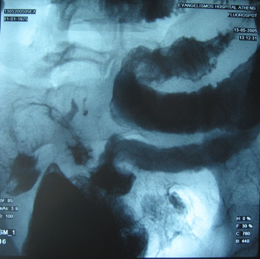

Στους ίδιους ασθενείς η εντερόκλυση μπορεί να αναδείξει ανάλογα ευρήματα με την ενδοσκοπική κάψουλα (εικόνες 36-43) ή να είναι φυσιολογική (εικόνες 44-48).

38  39

Εικόνα 38. Ο ίδιος ασθενής με τις εικόνες 10,13.          Εικόνα 39. Ο ίδιος ασθενής με τις εικόνες 33,34.

Στένωση τελικού ειλεού                                                  Εξελκώσεις τελικού ειλεού

40  41

Εικόνες 40,41. Ίδιος ασθενής με την εικόνα 17. Στένωση του αυλού του τελικού ειλεού με παρουσία

πολλαπλών ελκών του βλεννογόνου και εικόνα πλακόστρωτου